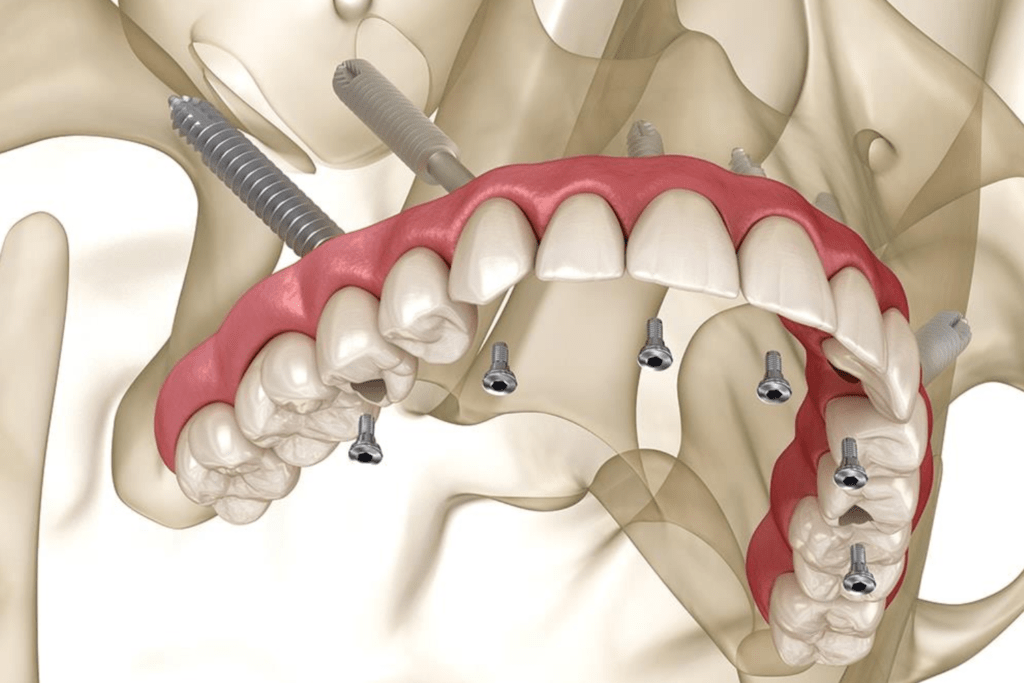

A special type of dental restoration is referred to as zygomatic implants, which are designed for patients with severe maxillary bone loss. These fixtures are surgically placed within the zygomatic bone, commonly known as the cheekbone, unlike conventional implants that are anchored in the jawbone. This alternative approach provides stability when traditional implantation isn’t possible because the bone structure doesn’t allow for conventional implants, and there’s no way to place them due to inadequate bone support. This allows for the creation of a stable foundation for the Dental prosthesis without any requirement of bone grafting. These implants are longer than traditional dental implants.

The Zygomatic implant procedure.

- Surgical placement – the surgery is performed under general anaesthesia or under local anesthesia. The type of Anesthesia depends on the patient’s and surgeon’s comfort ability. The surgeon makes small incision in the gum tissue and carefully dissect to reach the bone and places the zygomatic implants into the cheekbone. It is placed in a planned angulation and depth. In complicated cases a surgical guide is utilized to place the Implants.In many cases a temporary processes can be loaded immediately allowing you to leave the clinic with a full functional smile.